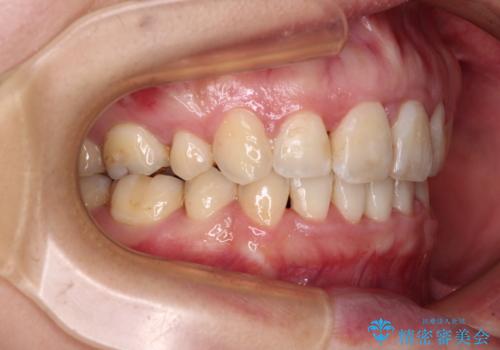

- 出っ歯と口の閉じにくさ、デコボコを気にして来院された患者様です。

口元の突出感を改善するため、上下左右第一小臼歯4本の抜歯を行い、ワイヤー装置による矯正治療を行うこととしました。

上下前歯の距離が大きかったため、上下の歯が接触するまでに時間がかかりました。

それでも目安である2年半で終えることができ、患者様には大変満足していただけました。